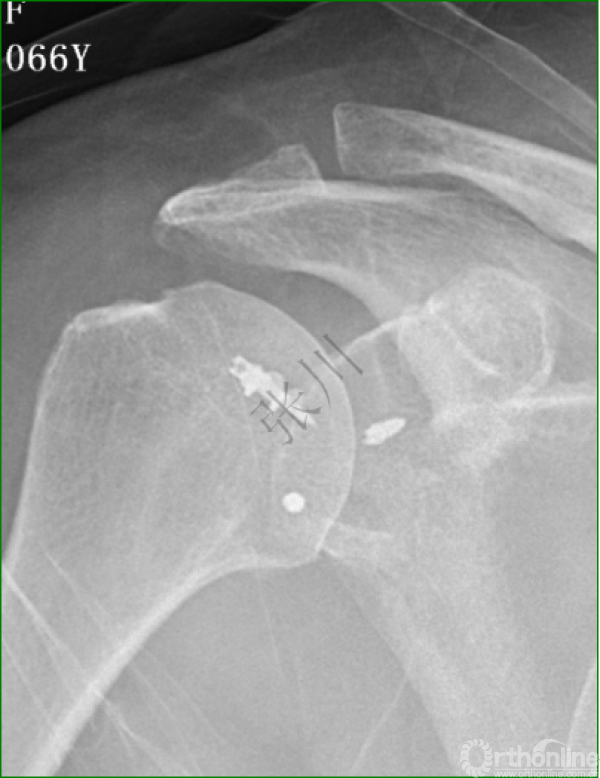

1.影像学评估

2.术后三个月超声评估

2.方法:Sugaya技术全关节镜下带线锚钉修复,两例应用Remplissage技术,3例应用5点钟和后外侧入路